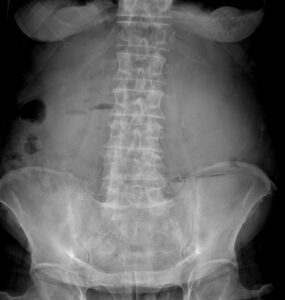

Rx AP bipedestación de abdomen.